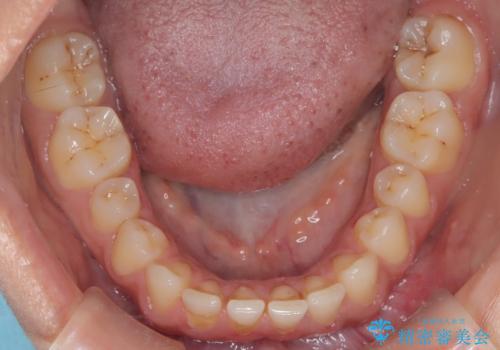

- 患者様は、前歯が出ている状態(上顎前突)と隙間を閉じたいというご希望で来院されました。診断の結果、骨格性の上顎前突が確認されたため、理想的には外科矯正が必要であることを説明しましたが、患者様の「非抜歯でできる範囲で治療を進めたい」という希望を尊重し、矯正治療計画を立てました。治療目標は、前歯の突出を可能な限り改善し、隙間を閉じることに重点を置きました。

本症例では、非抜歯での治療を選択したため、スペースを確保するためにIPR(歯間削合)を行い、歯列を整えました。オーバージェット(上の前歯と下の前歯の水平的なズレ)は残る結果となりましたが、見た目や機能の改善を重視し、患者様と治療計画を共有しながら進めました。治療中は、歯列全体のバランスと噛み合わせを考慮しつつ、矯正装置の適切な使用を徹底しました。当初の計画通りに治療を完了し、患者様にも満足していただけました。